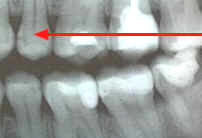

Técnica:

La cabeza del paciente se

coloca de manera que el plano de oclusión quede paralelo al del

piso. El rayo central se dirige al punto de contacto de los

dientes superiores con los dientes inferiores y paralelo a sus

superficies proximales, con el tubo formando un ángulo de 5 a

10º por encima del plano horizontal.

Ver figura 5. Para los dientes posteriores es

deseable tomar dos vistas de cada lado:

-

una en la que la película

se coloca más atrás para incluir el espacio inter-proximal

entre el segundo y el tercer molar,

y la otra lo bastante adelante

como para tomar la cara distal del canino. Solo necesita cuatro

películas para el diagnóstico de caries en todos los sectores

posteriores.

Cuando el tercer molar se

encuentra en proceso de erupción y se observa solo una parte de la

corona clínica a la inspección visual, es de utilidad diagnóstica

general, una imagen de una radiografía periapical de esa pieza

dental en particular.

Figura 5 |